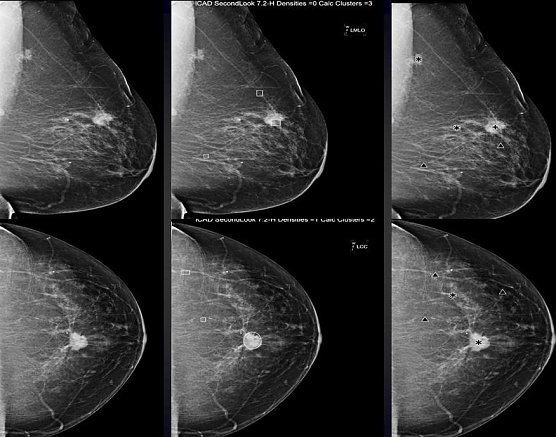

Hier sieht man links eine Röntgenaufnahme der weiblichen Brust mit einem bösartigen Tumor sowie in der Mitte und rechts jeweilige computerbasierte Analysen, die mit verschiedenen Programmen (R2 und iCAD) jeweilig auffällige Strukturen in der Röntgenaufnahme (Mammographie) markieren und für den Befunder hervorheben, Verdichtungen mit Stern bzw. Kreis sowie auffälligen Mikrokalk (kann auch mit Brustkrebs assoziiert sein) mit Dreieck bzw. Viereck (je nach Hersteller der Software unterschiedlich).

So wurden die Ergebnisse einer in Nordhausen betreuten Doktorarbeit vorgestellt. Diese Arbeit beschäftigte sich mit der computergestützten Erkennung auffälliger Strukturen in der Mammographie und analysierte hierbei vergleichend drei verschiedene derzeit in Nordhausen verfügbare Systeme. Zielstellung hierbei war, noch stärker als bislang ausschließlich auffällige Strukturen aus mammographischen Bilddaten herauszufiltern, die dann tatsächlich auch einem kleinen Karzinom oder einer Krebsvorstufe entsprechen, um so bei Patientinnen mit letztlich gutartigem Befund die bislang erforderliche klärende radiologische Brustbiopsie nicht mehr durchführen zu müssen.